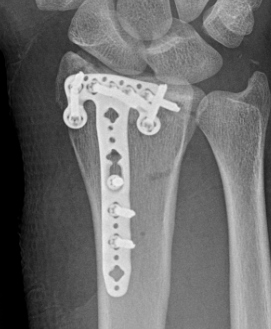

Fragment specific plates

| Volar locking plates | Volar rim plates | Radial styloid plates |

Locking screws act as fixed angle devices Variable angle screws |

For very distal fracture fragments

Supplementary radial column fixation |

Volar locking plate technique

- apply volar plate with screw fixation in scaphoid and lunate fragments

- ensure not beyond watershed line to avoid flexor tendon irritation / rupture

- engage dorsal cortex but not too long to prevent EPL rupture